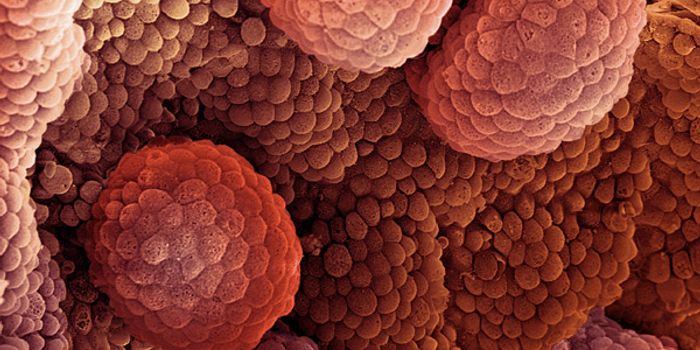

JUN 26, 2015CancerOne reason why cancer is so harmful is that it can trick "checkpoint" proteins found on the immune system's T cells, vir ...

JUN 18, 2015CancerAccording to the National Cancer Institute, prostate cancer is the most common cancer in men in the United States, after ...

AUG 12, 2015CancerResearchers at Baylor College of Medicine have developed a drug candidate that overstimulates proteins critical to tumor ...